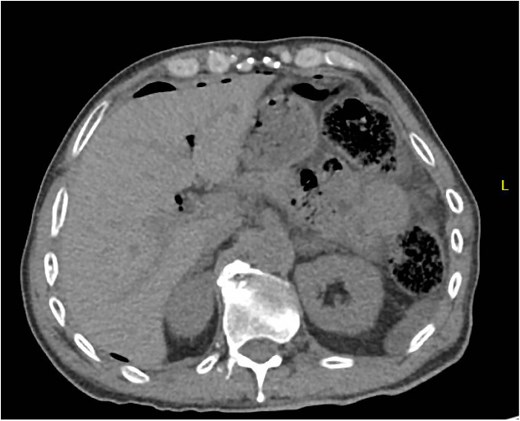

A 71 year old male presented to the hospital with abdominal pain and free air on initial CT scan (Fig. 5). Of note, the patient had a recent right total hip replacement 2 days prior by the orthopedic surgery team. The patient was taken emergently to the operating room and was found to have perforated sigmoid diverticulitis with feculent peritonitis. He underwent a left colectomy with primary anastomosis. The fascia was closed with #1 non looped PDS and interrupted figure of eight stitches. The umbilicus was reapproximated with sutures, and a negative pressure subcutaneous wound vac (black foam) was placed to the midline laparotomy incision and kept on continuous suction at -125mm Hg. The first wound vac change occurred on POD 4 (Fig. 6a) and then the wound was changed every other day similar to the above patients. DPC was performed on POD 11 (Fig. 6b). The patient’s intraoperative cultures grew E. coli and pseudomonas and he completed a 10 day course of antibiotics. The patient was discharged to acute rehab on POD 11. The patient was then seen in the office 10 days after discharge and DPC on POD 21. The midline incision was healing well and was without any signs of SSI (Fig. 6c).

Patient C. Initial CT abdomen and pelvis showing free air concerning for perforated hollow viscus.